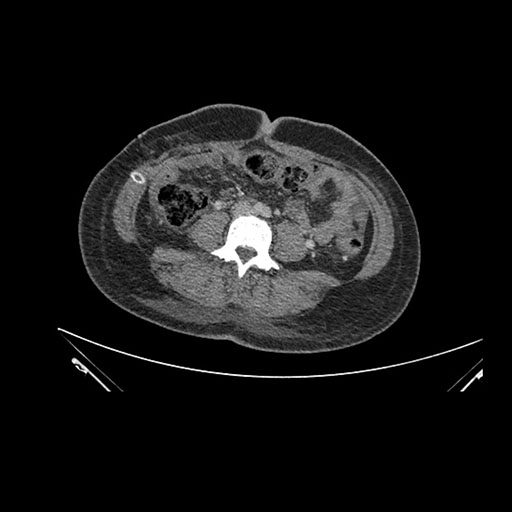

Imaging Analysis

Look through the patient's CT scan to identify any areas of concern for the necessary procedure.

Based on initial findings, which issue(s) would you be most concerned about?